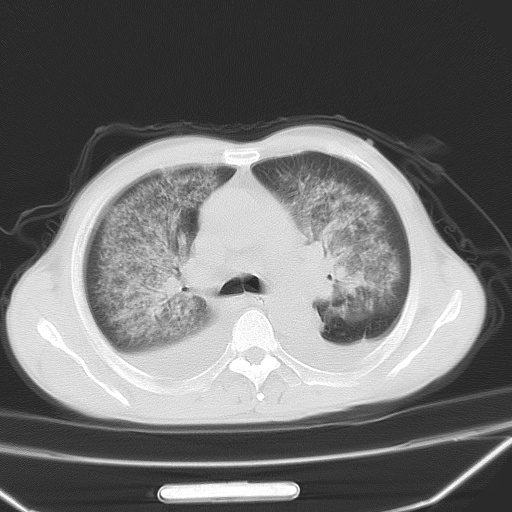

男、42岁、咯血3天。既往有甲亢、贫血、血尿蛋白尿史多年。血象:wbc:6.   中性粒:70.6%。

结合病史考虑双肺泡积血,双侧胸腔少量积液;肺水肿待排(肺水肿症状重)。

双肺堆成磨玻璃影,双测胸腔积液。考虑:肺水肿、间质性肺炎、真菌感染、ards、hiv感染、肺出血。

双肺野对称性磨玻璃影,分布于内中带,双侧胸水,患者有咯血。

双肺野广泛对称性磨玻璃影、实变影,以肺门为中心,主要分布于内中带,符合典型肺泡性肺水肿;伴双侧胸腔少量游离积液。结合患者既往病史且咯血就诊,支持多因素(尿毒症等)所致之肺水肿、肺出血、胸水;影像表现暂不考虑心源性水肿,且症状也不太符。需密切随诊结合临床治疗等进一步明确。

心影增大密度略低,双肺磨玻璃样高密度影及双侧胸腔积液,考虑心功能不全继发双肺肺水肿及双侧胸腔积液。心影密度略低,考虑贫血所致。